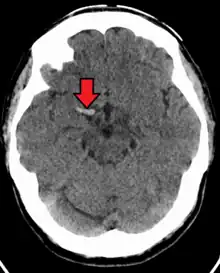

Stroke

Acute thrombus in the right MCA M1 branch

A stroke is the rapid decline of brain function due to a disturbance in the supply of blood to the brain.[10] This can be due to ischemia, thrombus, embolus (a lodged particle) or hemorrhage (a bleed).[10] In thrombotic stroke, a thrombus (blood clot) usually forms around atherosclerotic plaques. Since blockage of the artery is gradual, the onset of symptomatic thrombotic strokes is slower. Thrombotic stroke can be divided into two categories — large vessel disease or small vessel disease. The former affects vessels such as the internal carotids, vertebral and the circle of Willis. The latter can affect smaller vessels, such as the branches of the circle of Willis.